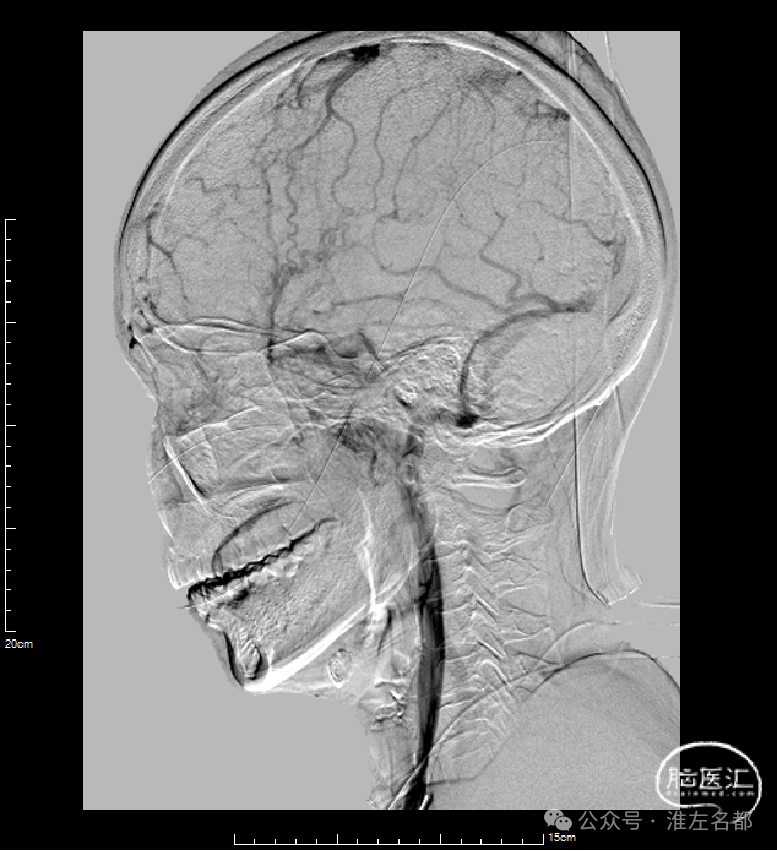

右侧颈动脉造影(正侧位):上矢状窦和直窦未见显影;右侧横窦和乙状窦少许显影。

左侧颈动脉造影(正侧位):上矢状窦前部少许显影,直窦未见显影,左侧横窦和乙状窦显影纤细。

介入治疗后右侧颈动脉造影:上矢状窦、直窦和右侧横窦-乙状窦均见显影,右侧横窦局部狭窄明显。